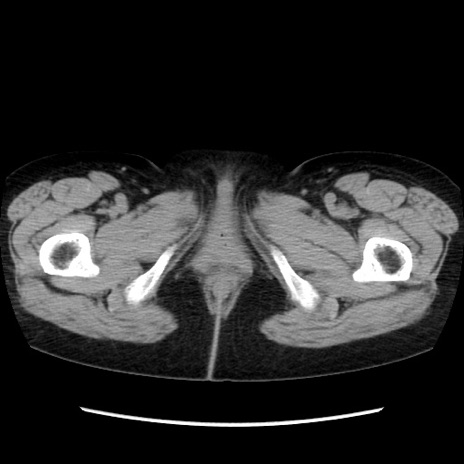

矢状断像

【症例】40歳代 女性

【主訴】上腹部痛、嘔気・嘔吐

【現病歴】約9時間前頃から急に上腹部痛、嘔気、嘔吐が出現。改善しないため救急要請。

【既往歴】子宮頚癌(広汎子宮全摘術、放射線療法)、腸閉塞

【身体所見】腹部:平坦、軟、腸雑音亢進、上腹部を中心に腹部全体に圧痛あり。

【データ】WBC 8400、CRP 0.03